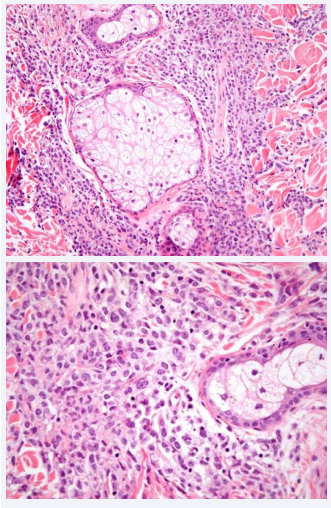

Figure 3: At higher magnification, an undifferentiated malignant infiltration of immature cells is observed.

The skin biopsy revealed an epidermis with no significant changes, with a well-defined Grenz zone. At higher magnification, the superficial and deep dermis were extensively infiltrated by neoplastic cells of hematolymphoid lineage surrounding the cutaneous appendages. These cells varied in size, with some appearing plasmacytoid and extending into the subcutaneous tissue. Immunohistochemistry showed positivity for lysozyme, myeloperoxidase, Ki67, CD43, and CD68 (Figure 4).

Histological diagnosis of MS needs a high index of suspicion and may elude detection in the absence of AML history. In our case, the diagnosis was confirmed through pathological examination and immunophenotypic detection. [10] Notably, neoplastic infiltration, densely observed in the dermis and fat, exhibits a tendency to circumvent vessels and adnexa, sparing the papillary dermis (Grenz zone). Cytological appearance varies dependent on origin and cellular maturation degree. Immunohistochemistry (IHC), notably including CD68, MPO, CD43, CD3, CD20, and chloroacetate esterase, constitute pivotal diagnostic tools [3].